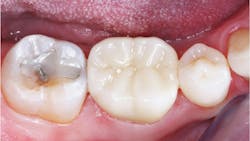

Hard and wear-resistant crown materials (figure 2) Restorative dentists dislike cutting off zirconia or lithium disilicate crowns because of their hardness and difficulty to cut. Do these two popular materials wear at a similar rate as tooth enamel? Clinicians Report Foundation’s research has shown that unglazed and unstained 3Y full-strength zirconia and lithium disilicate wear at the same rate as enamel (figure 3). However, when stain and glaze are placed on either material to produce better esthetics, the crowns wear the opposing teeth significantly. Almost all zirconia crowns of all iterations and lithium disilicate have stain and glaze placed on them. Other than 3Y full-strength zirconia, almost all other varieties of zirconia studied in vivo to date wear opposing enamel—glazed or not.1

Although porcelain-fused-to--metal (PFM) crowns also wear opposing enamel, the nearly total indirect restoration use of zirconia and lithium disilicate crowns causes varying degrees of wear, further contributing to changes in occlusion.